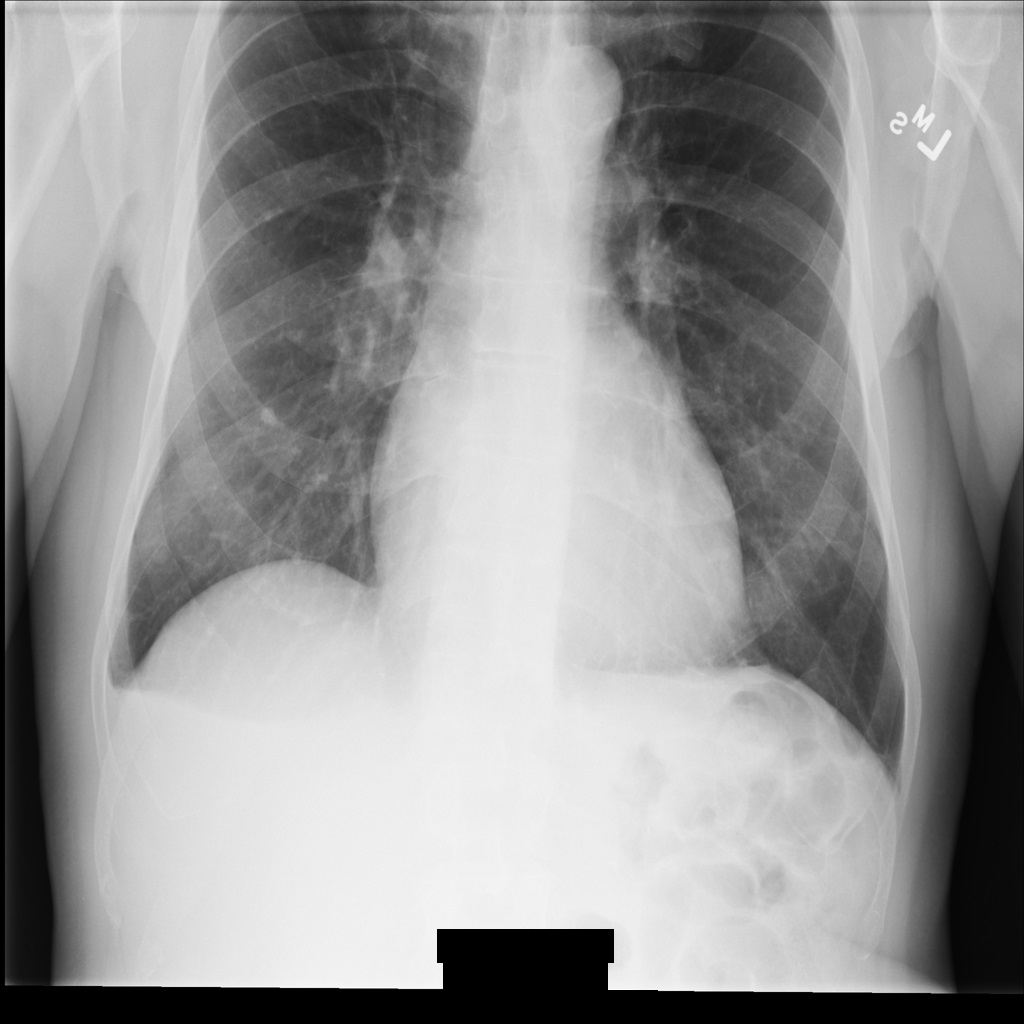

Exemple d'image

Certains exemples de cette page contiennent une sortie de l'image anonymisée. Chaque exemple utilise l'image d'origine suivante comme entrée. Vous pouvez comparer l'image de sortie de chaque opération d'anonymisation à cette image d'origine pour voir les effets de l'opération :